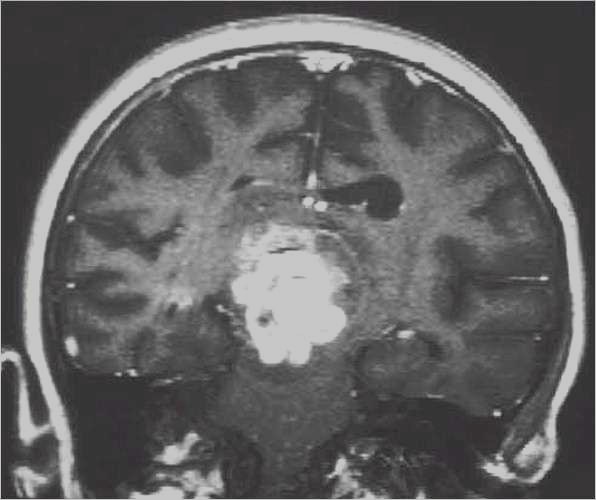

Glioma

ad alto grado di malignità (Glioblastoma) |

Lesioni caratterizzate da un accrescimento veloce con infiltrazione del tessuto cerebrale attiguo e diffusione a distanza di cellule maligne.

Scopo della chirurgia è ridurre macroscopicamente la massa tumorale per facilitare ulteriori trattamenti (principalmente radio - chemioterapia mentre altri protocolli terapeutici sono ancora in fase di studio).

In queste lesioni la loro conformazione anatomica, praticamente sempre di tipo II (Daumas-Duport) non ha un ruolo così dirimente nell'indicazione chirurgica poiché il comportamento biologico è sicuramente il fattore più importante.

RM:

glioma con segni di trasformazione maligna